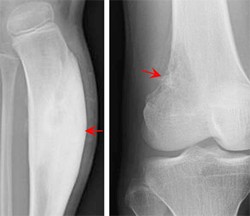

足跟骨质增生俗称为跟骨刺。它骨质增生症的一种,其症状是足根压痛,脚底疼痛,早晨重,下午轻,起床下地第一步痛不可忍,时轻时重,走路时脚跟不敢用,有石硌、针刺的感觉,活动开后…「查看详情」